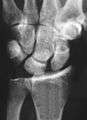

Stress view showing scapholunate instability

Scapholunate ligament disruption associated with a colles fracture

Scapholunate disassociation

Complete rupture of this ligament leads to wrist instability.[3][4] The instability can be either dynamic in nature which typically cannot be seen on X-Ray, or static which can be seen on X-Ray. The Watson's test may be used in diagnosis.